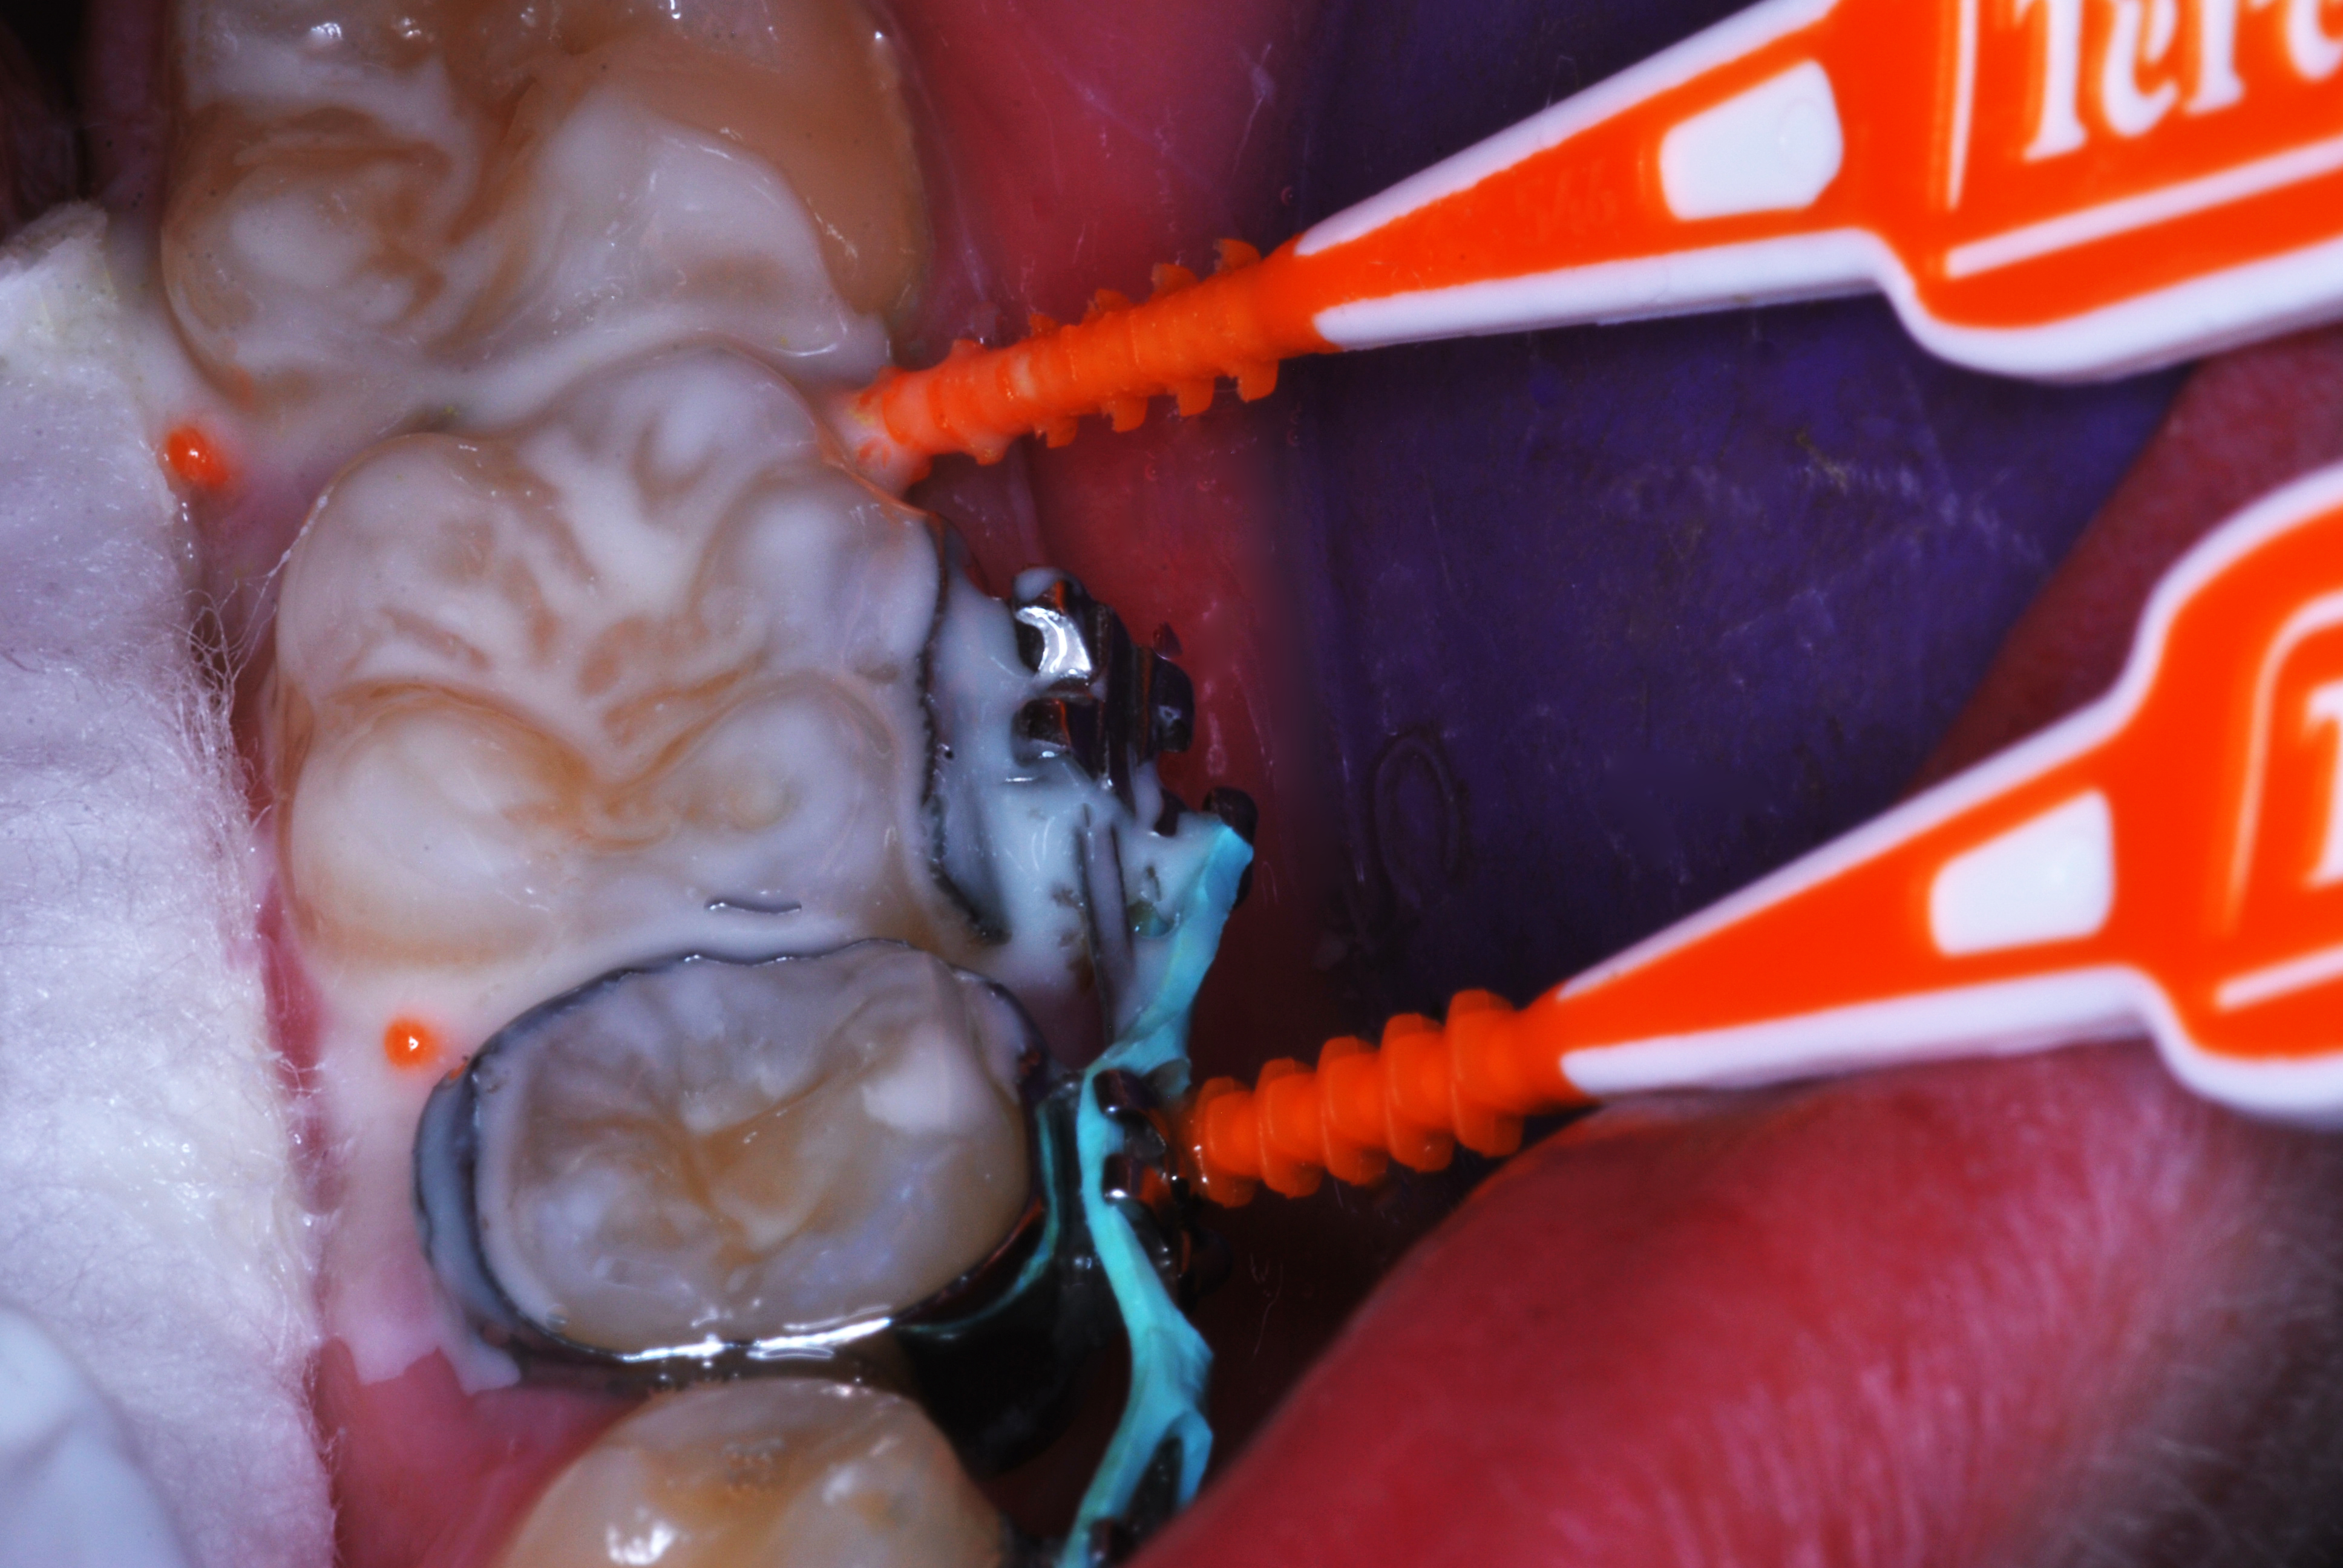

(6.) After exposure of disto-occlusal caries, SDF is applied, followed by a coating of fluoride varnish.

Figure 6

(7.) After exposure of disto-occlusal caries, SDF is applied, followed by a coating of fluoride varnish.

Figure 7

(8.) After exposure of disto-occlusal caries, SDF is applied, followed by a coating of fluoride varnish.

Figure 8